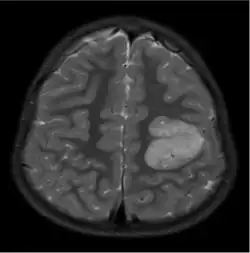

The neurological features of AG tumors are visible via CT scanning or MRI. A clear indication of AG may appear as well-delineated, solid, T2-hyperintense, non-enhancing cortical lesions located in the temporal or frontal lobes in MRI.[1] Another diagnostic trait is a stalk-like extension to adjacent brain ventricles.[13] These traits are similar to low-grade gliomas from a radiological perspective.

The results from CT scanning and MRI are different in terms of clarity and effectiveness of diagnosis. AG displays an expansive non-enhancing cortical tumor in CT scanning, whereas MRI shows a relatively clearer appearance of AG and the tumors appear to be infiltrative, well-defined, and hypointense with T1 lesion.[4] T2/FLAIR lesions indicate AG as a tumor tissue with some extension toward the ventricles along vessels.[4] The possibility of cystic-appearing areas exists as well. In some cases, MRI results show an increase in ribbon-like signal on T1W1 lesions.[4] The clear radiographic outcomes of MRI makes it the more widely used option in the diagnosis of AG.[4]

Nevertheless, precise diagnosis of AG from other phenotypically similar gliomas (such as astroblastoma or ganglioglioma) is a challenge merely based on MRI or CT scanning.[14] The main difference between AG and ganglioglioma could be only AG shows enhancement over time. Compared to AG, astroblastoma often has a discrete border in epithelioid cells and shows vascular sclerosis symptoms.[15]